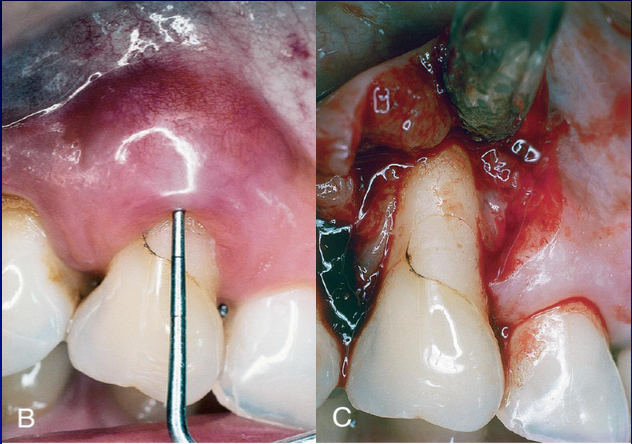

periodontal abscess

localized purulent infection w/in the tissues adjacent to the periodontal pocket that may lead to the destruction of periodontal ligament and alveolar bone. Usually pre-existing chronic periodontitis present!!! Occlusion of pocket orifice.

Clinical featuers: smooth, shiny swelling of the gingiva, painful, tender to palpation, purulent exudate, increased probing depth, mobile and/or percussion sensitive, tooth usually vital

A PERIODONTAL EVALUATION FOLLOWING RESOLUTION OF ACUTE SYMPTOMS IS ESSENTIAL!!!